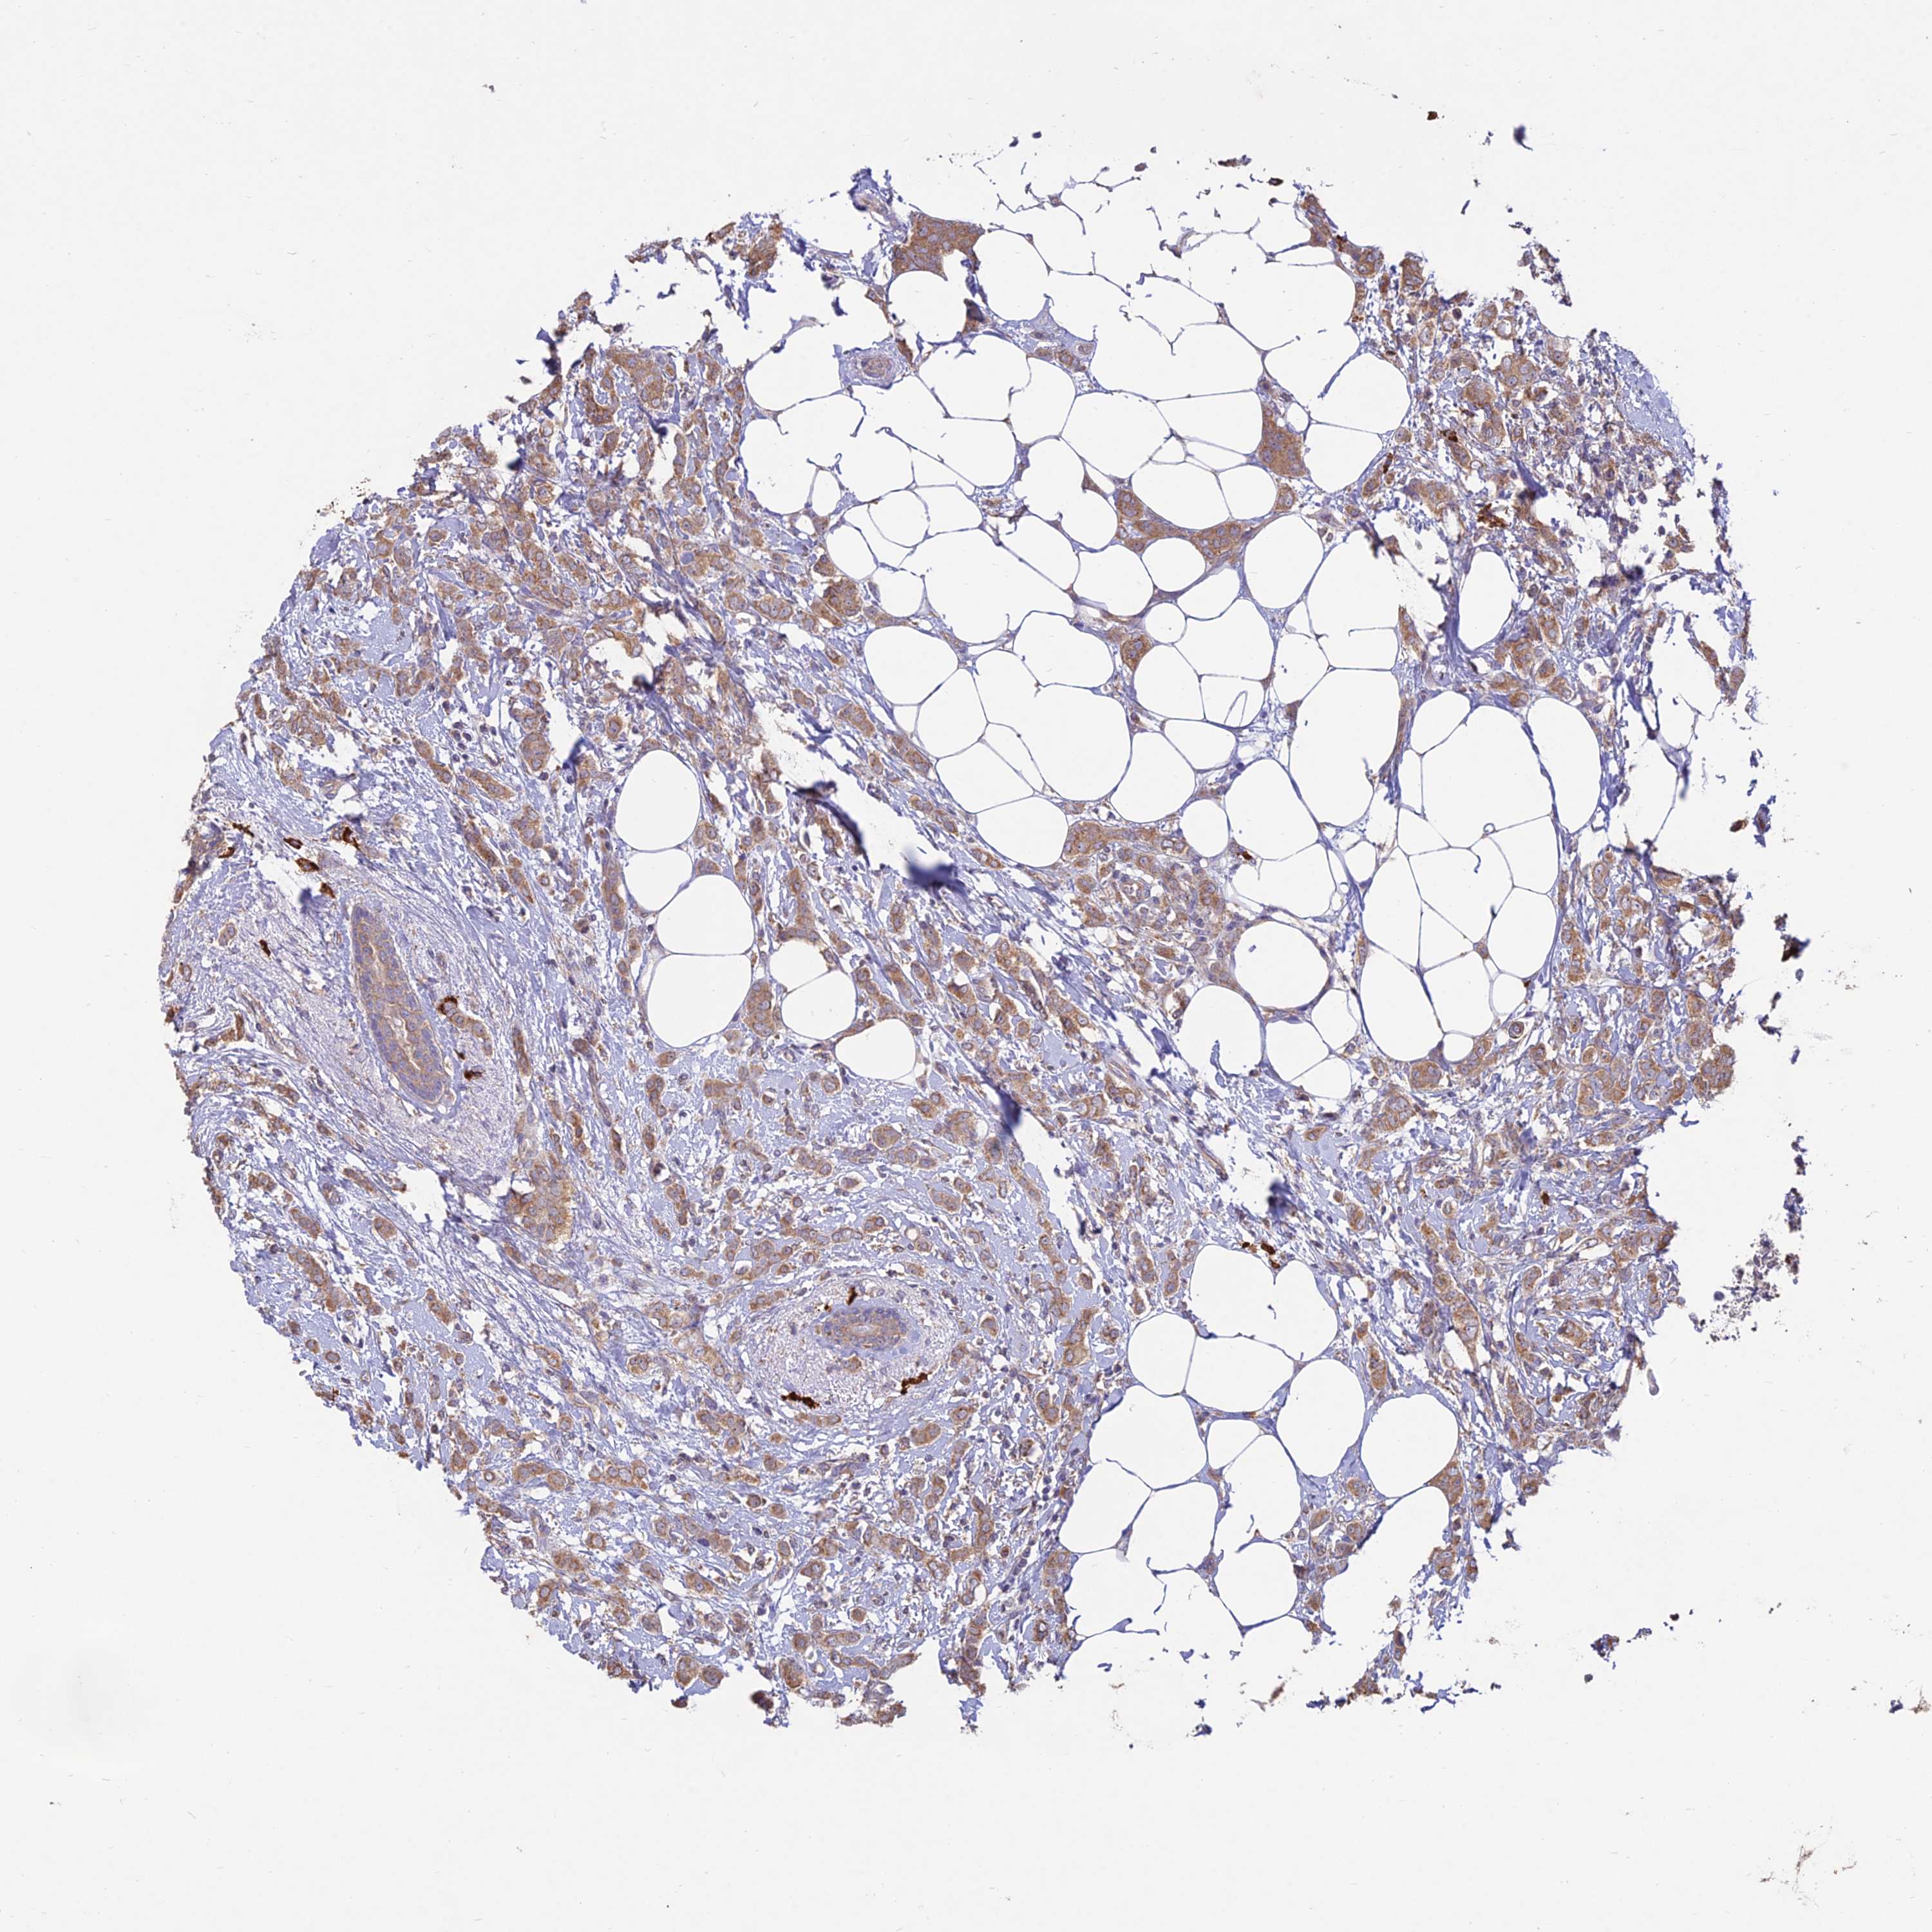

BRCA TCGA BRCA VALIDATION PROTEIN EXPRESSION

ANTIBODIES

AND

VALIDATION